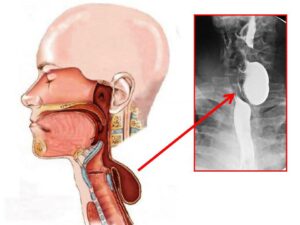

В Алматинской многопрофильной клинической больнице проведена уникальная операция пациенту 1954 года рождения, который более 30 лет страдал нарушением глотания. Диагноз – дивертикул Ценкера, редкая патология, встречающаяся примерно у 3,5% пациентов с заболеваниями пищевода.

Мужчина на протяжении десятилетий испытывал серьёзные трудности при приёме пищи. Последние годы состояние резко ухудшилось: пища застревала, приходилось самостоятельно надавливать на шею, чтобы она частично проходила в желудок. Остальное выходило наружу с рвотой. За последние 2–3 года пациент потерял около 20 кг и оказался на грани истощения.

«Дивертикул Ценкера — серьёзная и коварная патология. Пациенты годами живут с дисфагией, не зная точного диагноза. В данном случае операция была крайне необходима, поскольку речь шла не только о качестве, но и о сохранении жизни. Мы рады, что пациент успешно перенёс лечение», — отметил врач.